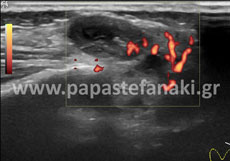

Υπέρηχοι οσχέου

Προετοιμασία ασθενούς Δεν απαιτείται.

• Οσχέου

Δεν απαιτείται προετοιμασία.